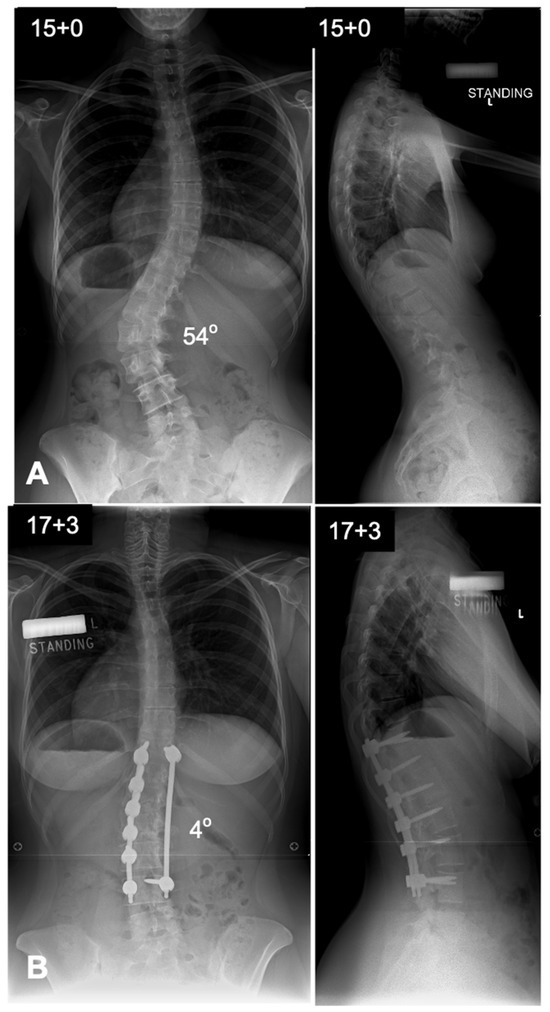

7. Anterior Versus Posterior Fusion in Lenke Type 5 Curves

Lenke 5 AIS, characterized by a primary thoracolumbar/lumbar [TL/L] curve with a compensatory thoracic curve, can be managed with either anterior spinal fusion [ASF] (Figure 6) or posterior spinal fusion [PSF] (Figure 7). The key argument favoring ASF is that it allows for shorter fusion constructs, potentially preserving an additional distal motion segment, which may reduce the risk of low back pain in later life if the fusion can be stopped at L3 rather than L4 [16]. Several studies have compared these approaches, showing that ASF achieves comparable coronal correction with fewer fused segments [17]. However, PSF, facilitated by modern segmental pedicle screw constructs, has become the standard approach due to its technical familiarity and ability to provide superior three-dimensional correction, particularly in terms of lumbar lordosis and thoracic kyphosis restoration [11,18]. Previous studies have indicated a greater loss of sagittal plane correction over time after ASF compared to PSF [17]. Additionally, PSF has been associated with better compensatory thoracic curve correction and improved trunk shift realignment [16,17]. Importantly, factors such as curve magnitude, lowest instrumented vertebra angle, and apical vertebra translation influence the decision on how far to extend the fusion distally. A predictive equation has been developed to guide this decision in PSF, helping to determine whether stopping at the Cobb-to-Cobb levels of the curve is sufficient or if additional distal levels should be included, in which case there may be an indication to consider performing an ASF instead [18]. Ultimately, both approaches have their strengths, and the choice should be individualized based on patient anatomy, surgical goals, and the surgeon’s expertise.